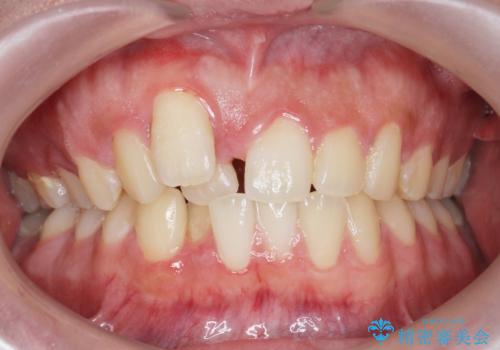

[セラミック治療] 前歯の審美治療に伴う矯正治療